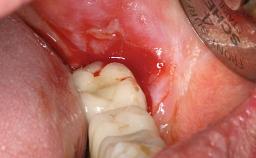

A healthy 31-year-old female patient presented with a failing maxillary left lateral incisor crown. The crown regularly loosened, and the remaining tooth was neither restorable nor rational to treat. The patient had a high smile line, a medium soft tissue biotype with a compromised mesial papilla (shorter than the contralateral one), and a horizontal scar in the buccal soft tissue as a result of past periapical surgery.

Previous surgeries in planned implant site Previous procedures resulting in none or minimal bone and soft tissue changes.

Soft Tissue Quality Presence of minimal scars/no inflammation

Papilla Deficient

Soft tissue anatomy Soft-tissue defects